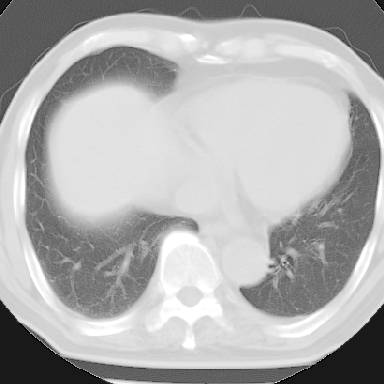

纵隔窗呢?慢支炎肺气肿;余未见明显渗出及占位!

慢性支气管炎、肺气肿。

慢性支气管炎并肺气肿

不支持慢性支气管炎,另外慢性支气管炎的诊断需结合临床病史才能诊断。

就以上的片子,如果没有明确的病史,说未见明显异常也不过份吧

这份病例诊断慢支并气肿可能属过诊,首先慢支的临床诊断标准是严格的,应该弄清楚,其次ct表现是否符合该病表现,本例老年人ct肺窗表现应属正常,不要跟着临床跑。